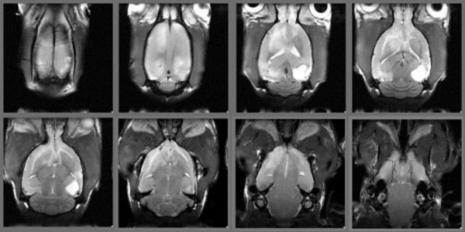

- アカゲサルの resting state fMRI

Oxytocin 投与前後の functional connectivity(oculomotor network の cross correlation)

アカゲザル(n=2)のグループ解析 - ラットのresting state fMRI